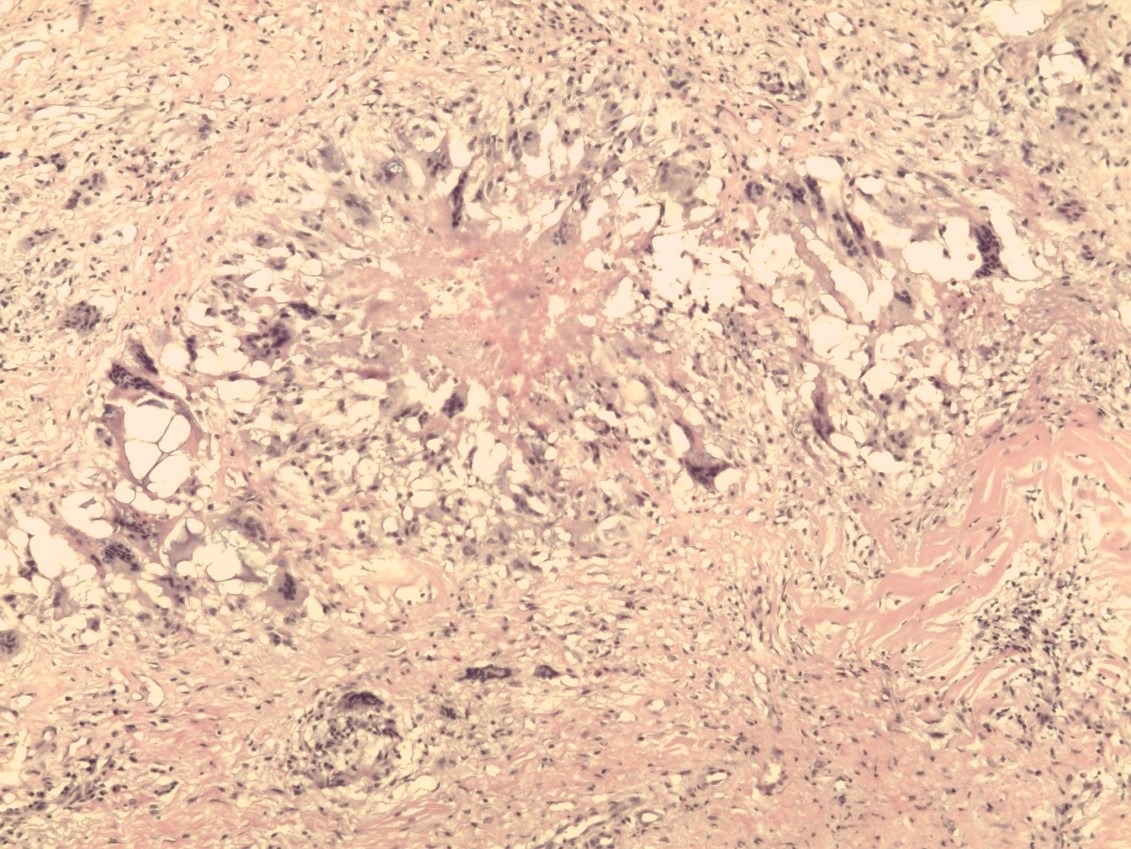

Гистологическая картина ПАМС до начала комплексного лечения была типичной и совпадала с описаниями других исследователей [22–26]. По всем полям визуализировали скопления гомогенных инородных тел (ПААГ), характер которых зависел от количества введенного геля, глубины и давности его залегания в мягких тканях, а также интенсивности его межтканевой миграции (рис. 1). Вокруг больших массивов безоболочечного имплантата, в основном сохранившего свою гомогенную базофильную структуру, прослеживалась тонкая соединительнотканная капсула толщина 50–120 мкм. Она состояла из нескольких слоев коллагеновых волокон и фибробластов (рис. 2). Толщина капсулы была неодинаковой на всем протяжении. На некоторых участках заметно выраженное ее истончение, разволокнение, дегенеративные изменения вплоть до полного перерыва (рис. 3). Последнее было особенно заметно у пациенток с длительным, свыше 10 лет, анамнезом «гелевой» болезни, а также при миграции ПААГ в соседние области.

Рис. 1. Биоптат ткани молочной железы: визуализируются скопления полиакриламидного геля диффузного и очагового характера. Окраска гематоксилином и эозином (×200).